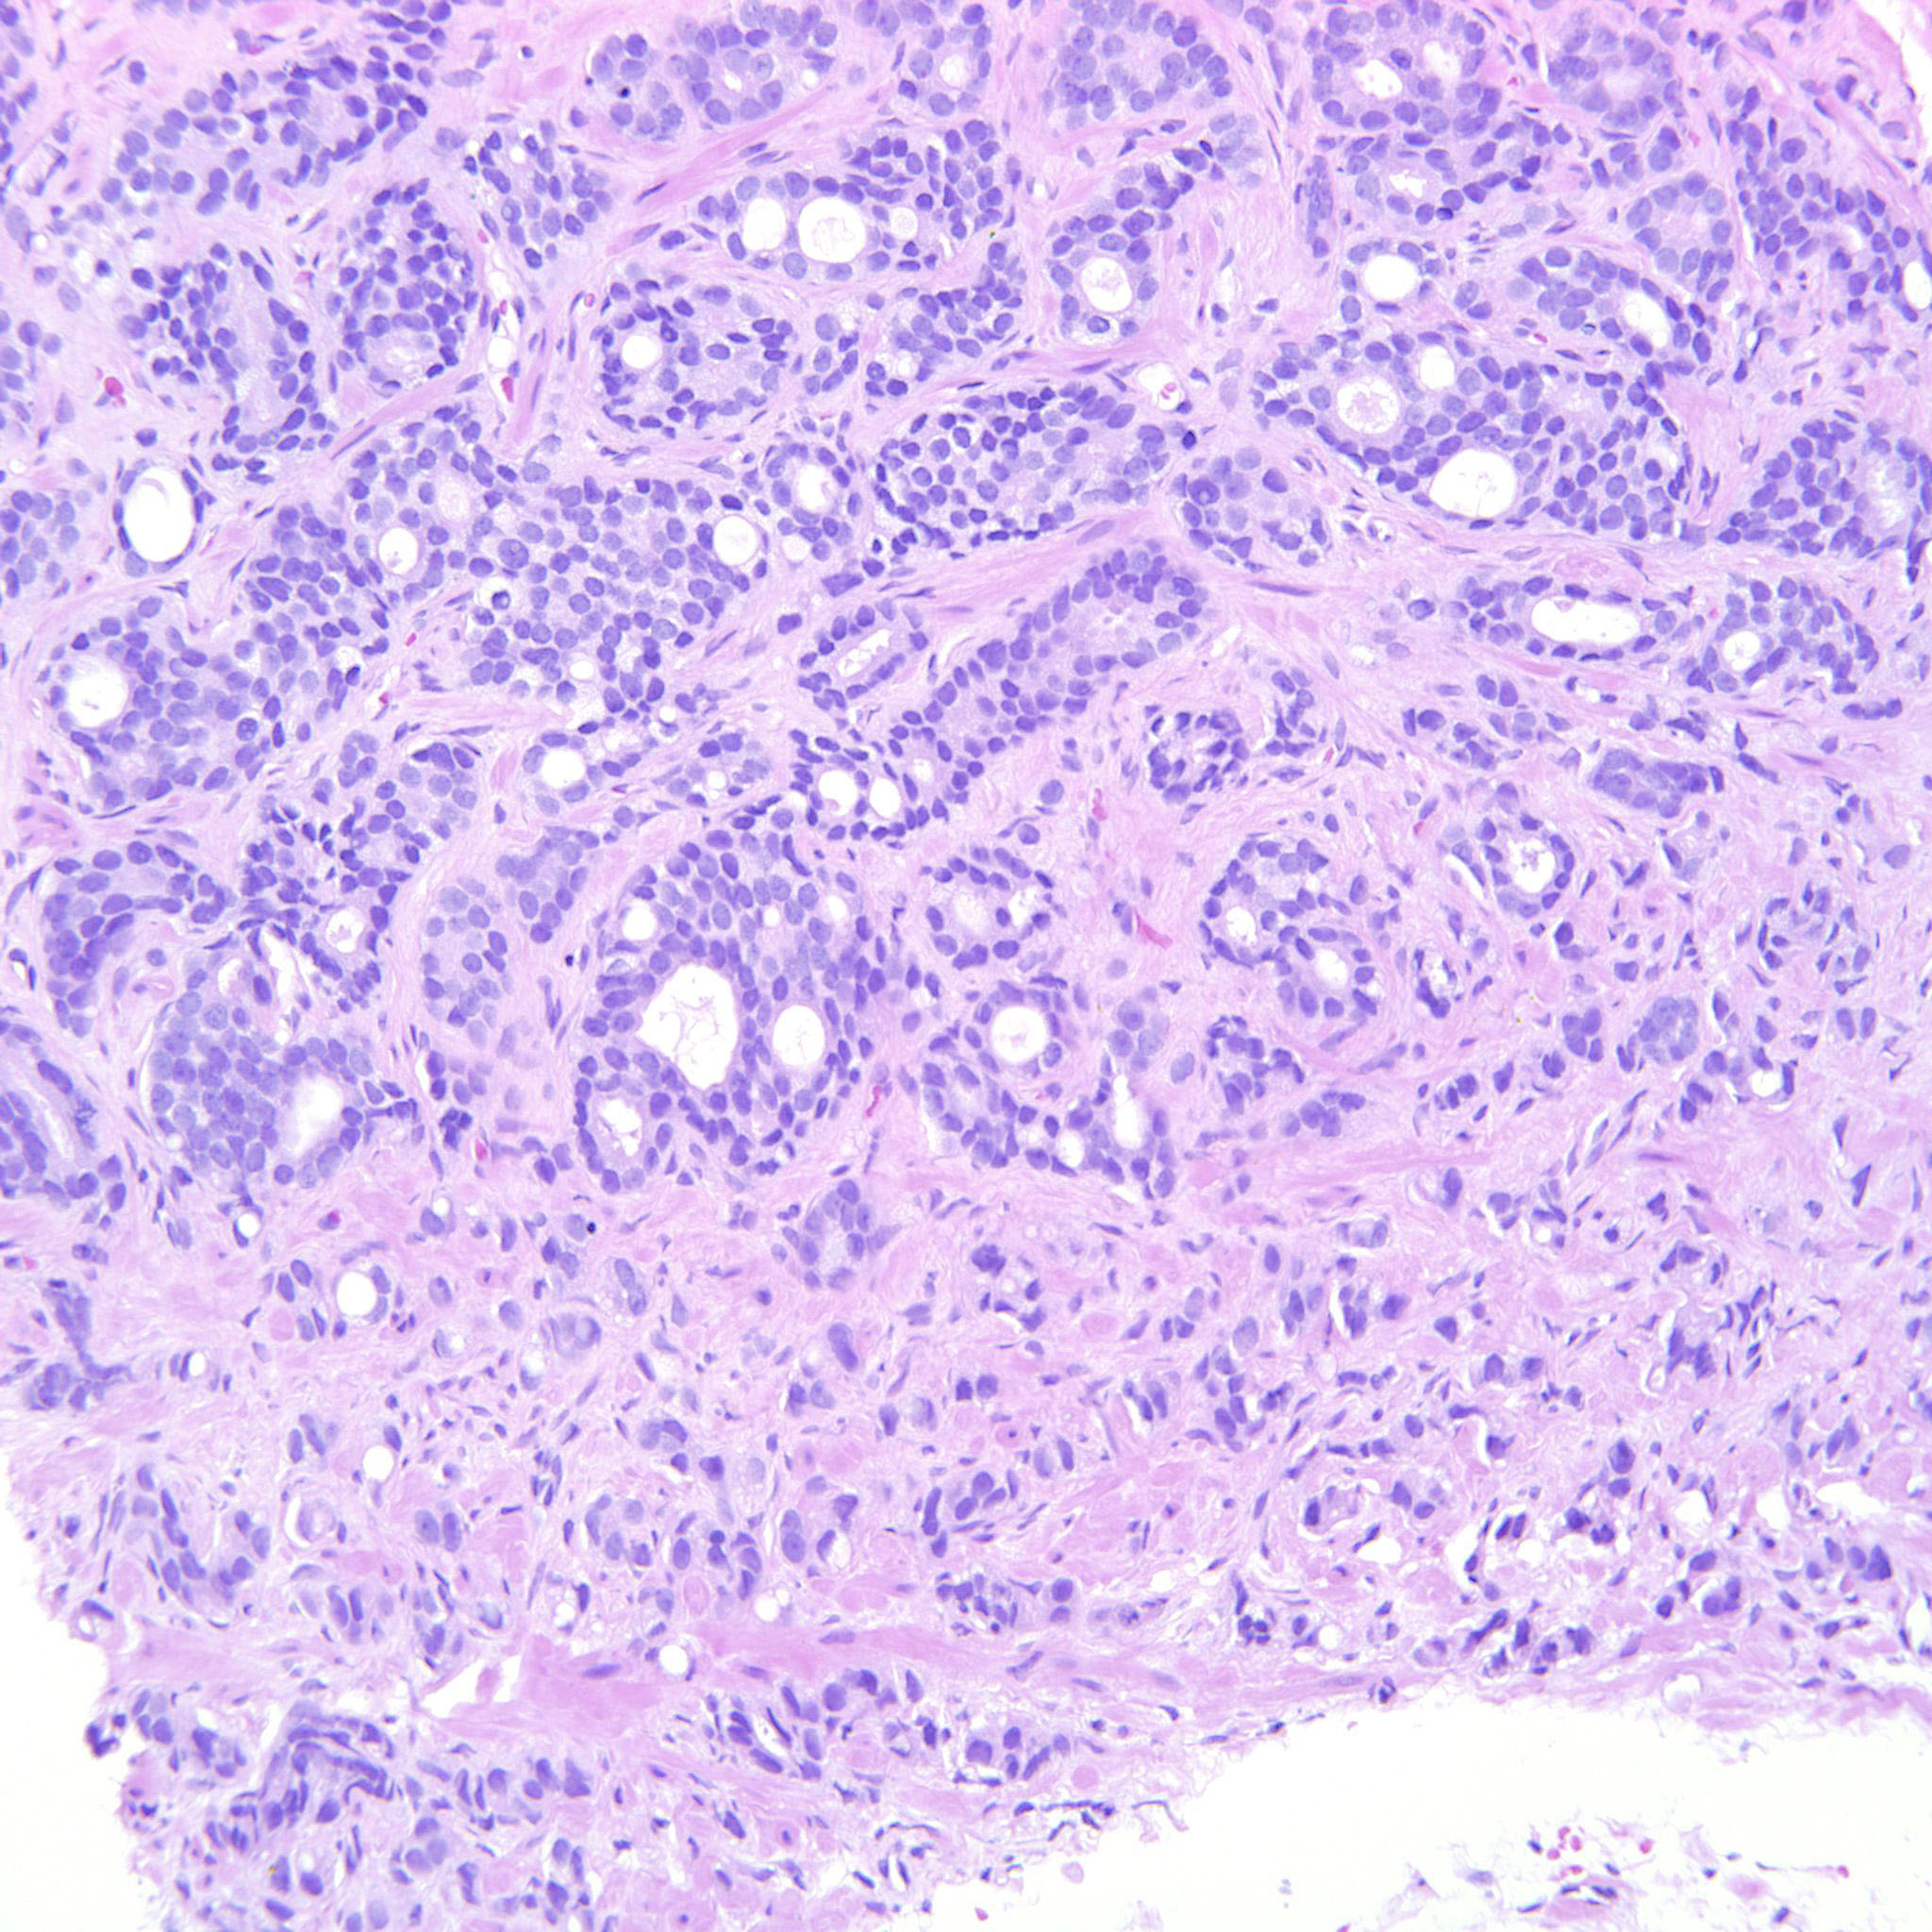

Consensus grade: GS 9-10 (ISUP 5)

Case description (by case creator):

The tumor is dominated by GP4 with mainly cribriform and fused glands but also some poorly formed glands. There is also a component of GP5 with single cells and indian files. These cells occupy an area that can be seen already at 10x. The GP5 component looks immature but is not suspicious for small cell carcinoma.